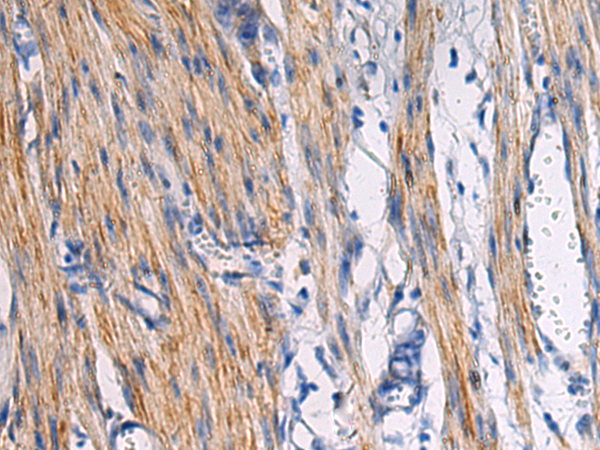

分类: 科研抗体货号: P13443别名:应用: WB,IHC反应种属: Human